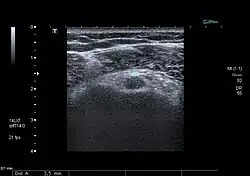

_019.jpg)

An der Größe des Muskels wird gerne die Kraft eines Menschen beurteilt. So gehört es zum „Imponiergehabe eines Kraftprotzes [...], den Bizeps gewaltig anschwellen zu lassen“[1]. Dabei ist zu beachten, dass er beim Anwinkeln des Armes jedoch nicht nur aufgrund seiner Dicke vorspringt, sondern auch, weil er von seiner Unterlage (dem Oberarmknochen) abgehoben wird, sobald der Ellenbogen gebeugt wird.[3]